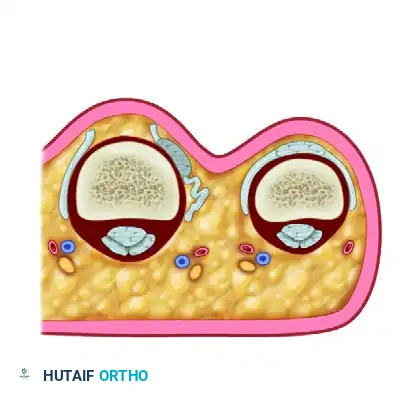

3. Metacarpophalangeal Joint Synovectomy

Synovectomy is the cornerstone of halting disease progression.

* Dissect between the synovial pannus and the joint capsule.

* Excise the hypertrophic synovium comprehensively. Pay special attention to the synovium herniating through the capsule and draping over the dorsal neck of the metacarpal. In severe rheumatoid cases, the dorsal capsule is often so attenuated and infiltrated by disease that the majority of it must be excised alongside the synovium.

* Abrasion Technique: The synovium frequently burrows under the collateral ligaments at the metacarpal head. Remove this inaccessible tissue by abrasion: wrap two or three layers of a rough gauze sponge over the point of a curved hemostat and vigorously sweep it through the recesses beneath the collateral ligaments.